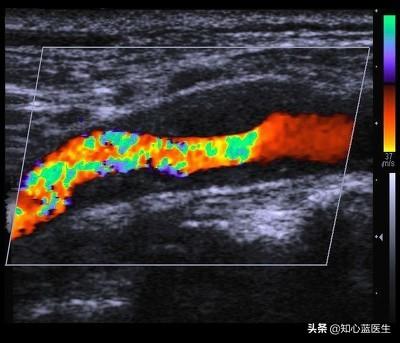

プラークの反転は、研究が進むにつれて再定義されてきた。すなわち、プラークサイズの縮小とプラークの安定性の向上である。利用可能なデータは,実験動物におけるアテローム性動脈硬化病変が,一定期間の投薬とアテローム誘発性食物の中止によって完全に退縮する可能性さえあることを示している。ヒトでは、血管造影や管腔内超音波検査によって、危険因子を一定期間コントロールし治療すると、初期のアテローム性動脈硬化病変が部分的に退縮することが確認されている。

動脈硬化とは、動脈血管の変性変化のことで、加齢とともに徐々に増加し、60歳以上の半数が動脈硬化であるといっても過言ではありません。多くの人は自覚症状がなく、頸動脈超音波検査や心臓超音波検査などの検査を受けて初めて発見されます。動脈硬化については、次のようなことを知っておくとよいと思います。

アテローム性動脈硬化症とは、血液中の脂質成分が動脈の内膜の下に沈着することである。川岸に堆積した細かい土砂や、錆びが付着した使い古しの金属パイプのようなものだ。

動脈硬化が深刻かそうでないかを見極めるには、より専門的な知識が必要であり、循環器疾患の専門家でない医師にとっては、あまり簡単な問題ではありません。したがって、ここではあまり具体的な方法は教えません。一般に、50%以上の閉塞を伴う症候性アテローム性動脈硬化症で、超音波やCTで "軟らかいプラーク "が認められる場合は、深刻に受け止め、さらに専門医に相談すべきである。